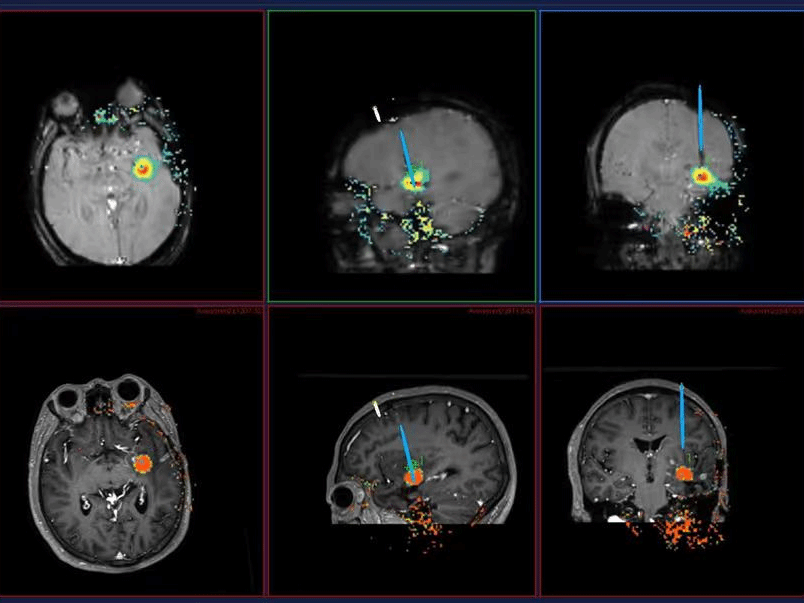

微创新技术:不开颅便可“消灭”脑深部胶质瘤

近日,在珠江医院手术室内,一场微创脑胶质瘤手术正在进行。一根直径不足1毫米的激光光纤,在机器人辅助下精准穿入大脑深处,直达靶点,在磁共振实时监测下消除病灶。术后患者林先生头皮仅留一个微小穿刺点,第三天顺利出院。这是珠江医院脑胶质瘤诊疗中心最新开展的磁共振引导激光间质热疗(LITT)技术,治疗深部胶质瘤的场景。肿瘤位于脑深部“雷区” 传统手术风险高近日,40多岁的林…